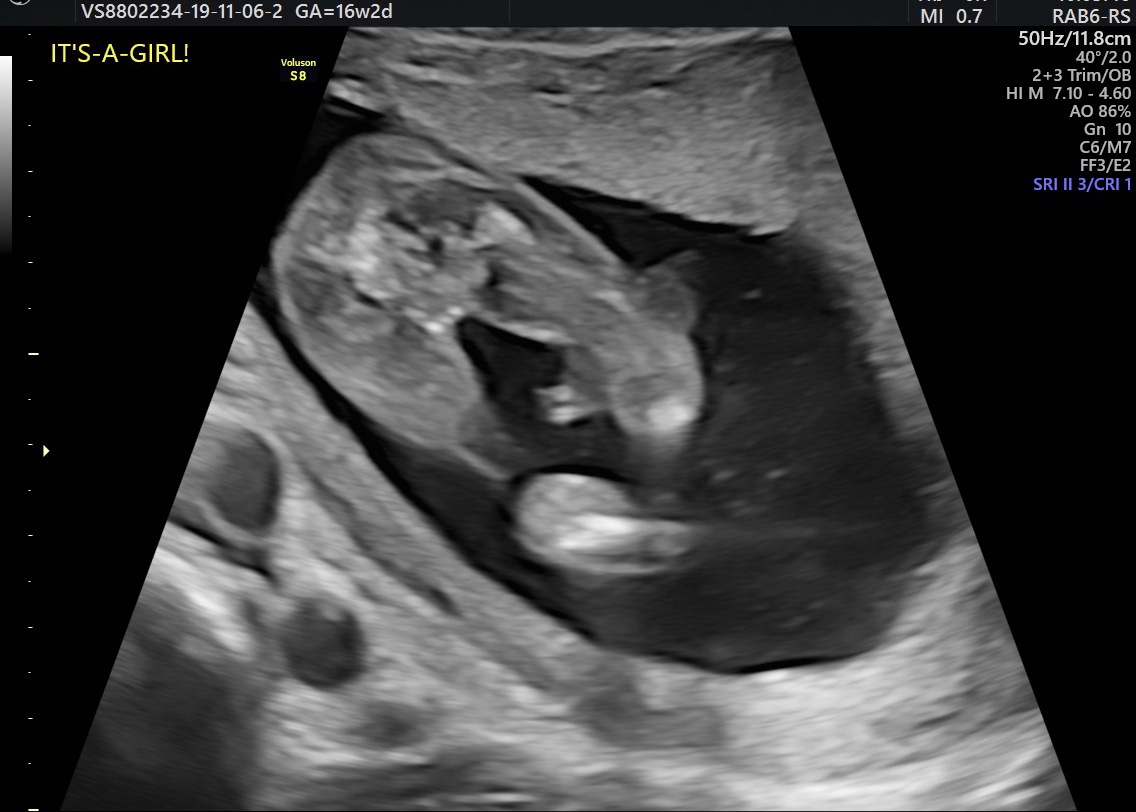

First post here but long time lurker. I had a 16 week uktrasound yesterday and the sonographer thought this was a girl but I just can’t believe it. What do you think, I don’t want to start telling people until we’re extra sure.

Thanks xAttachment 42076